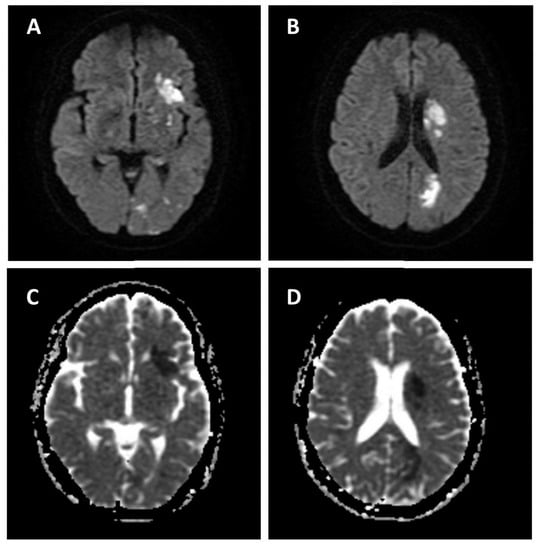

2. Case Presentation